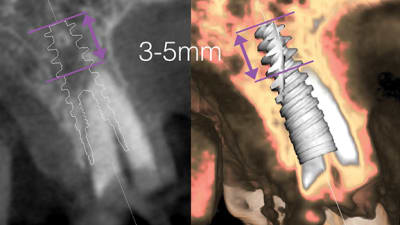

Online Only Online Only Implantology Immediate Implant Placement and Provisionalization Using the Patient’s Extracted Crown: 12-Month Follow-Up By Carlos Eduardo Edwards Rezende, PhD, Denise Piotto Leonardi, PhD, Fernando Luis Esteban Florez, PhD, Flávia Tomazinho, MS, Gilmar José Begnini, MS, Tatiana Miranda Deliberador, DDSPhD March 01, 2018 12 min read